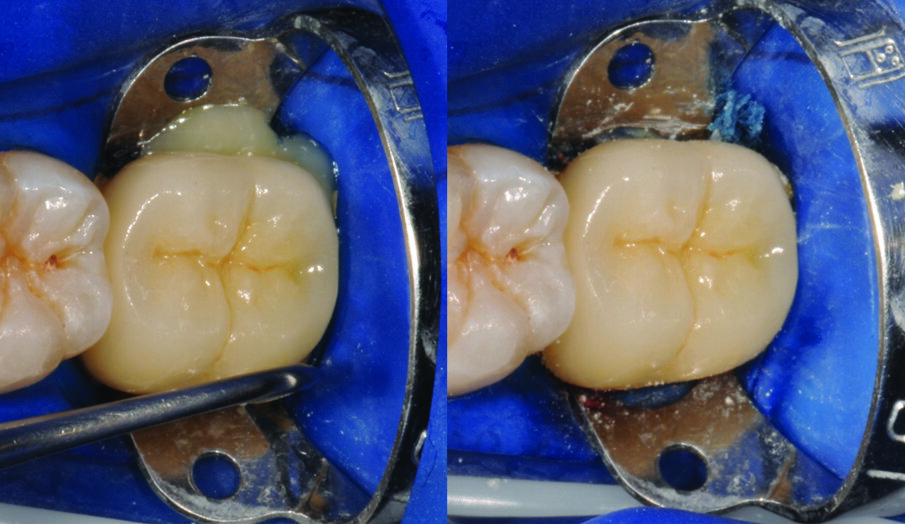

Fig. 6: Tooth preparation after rubber dam placement for isolation.

Fig. 7: Apply 3M™ Single Bond Universal Adhesive to the bonding surface rubbing it in for 20 seconds.

Fig. 8: Gently air thin adhesive with oil-free air for five seconds until the solvent is evaporated and no more ripples are observed.